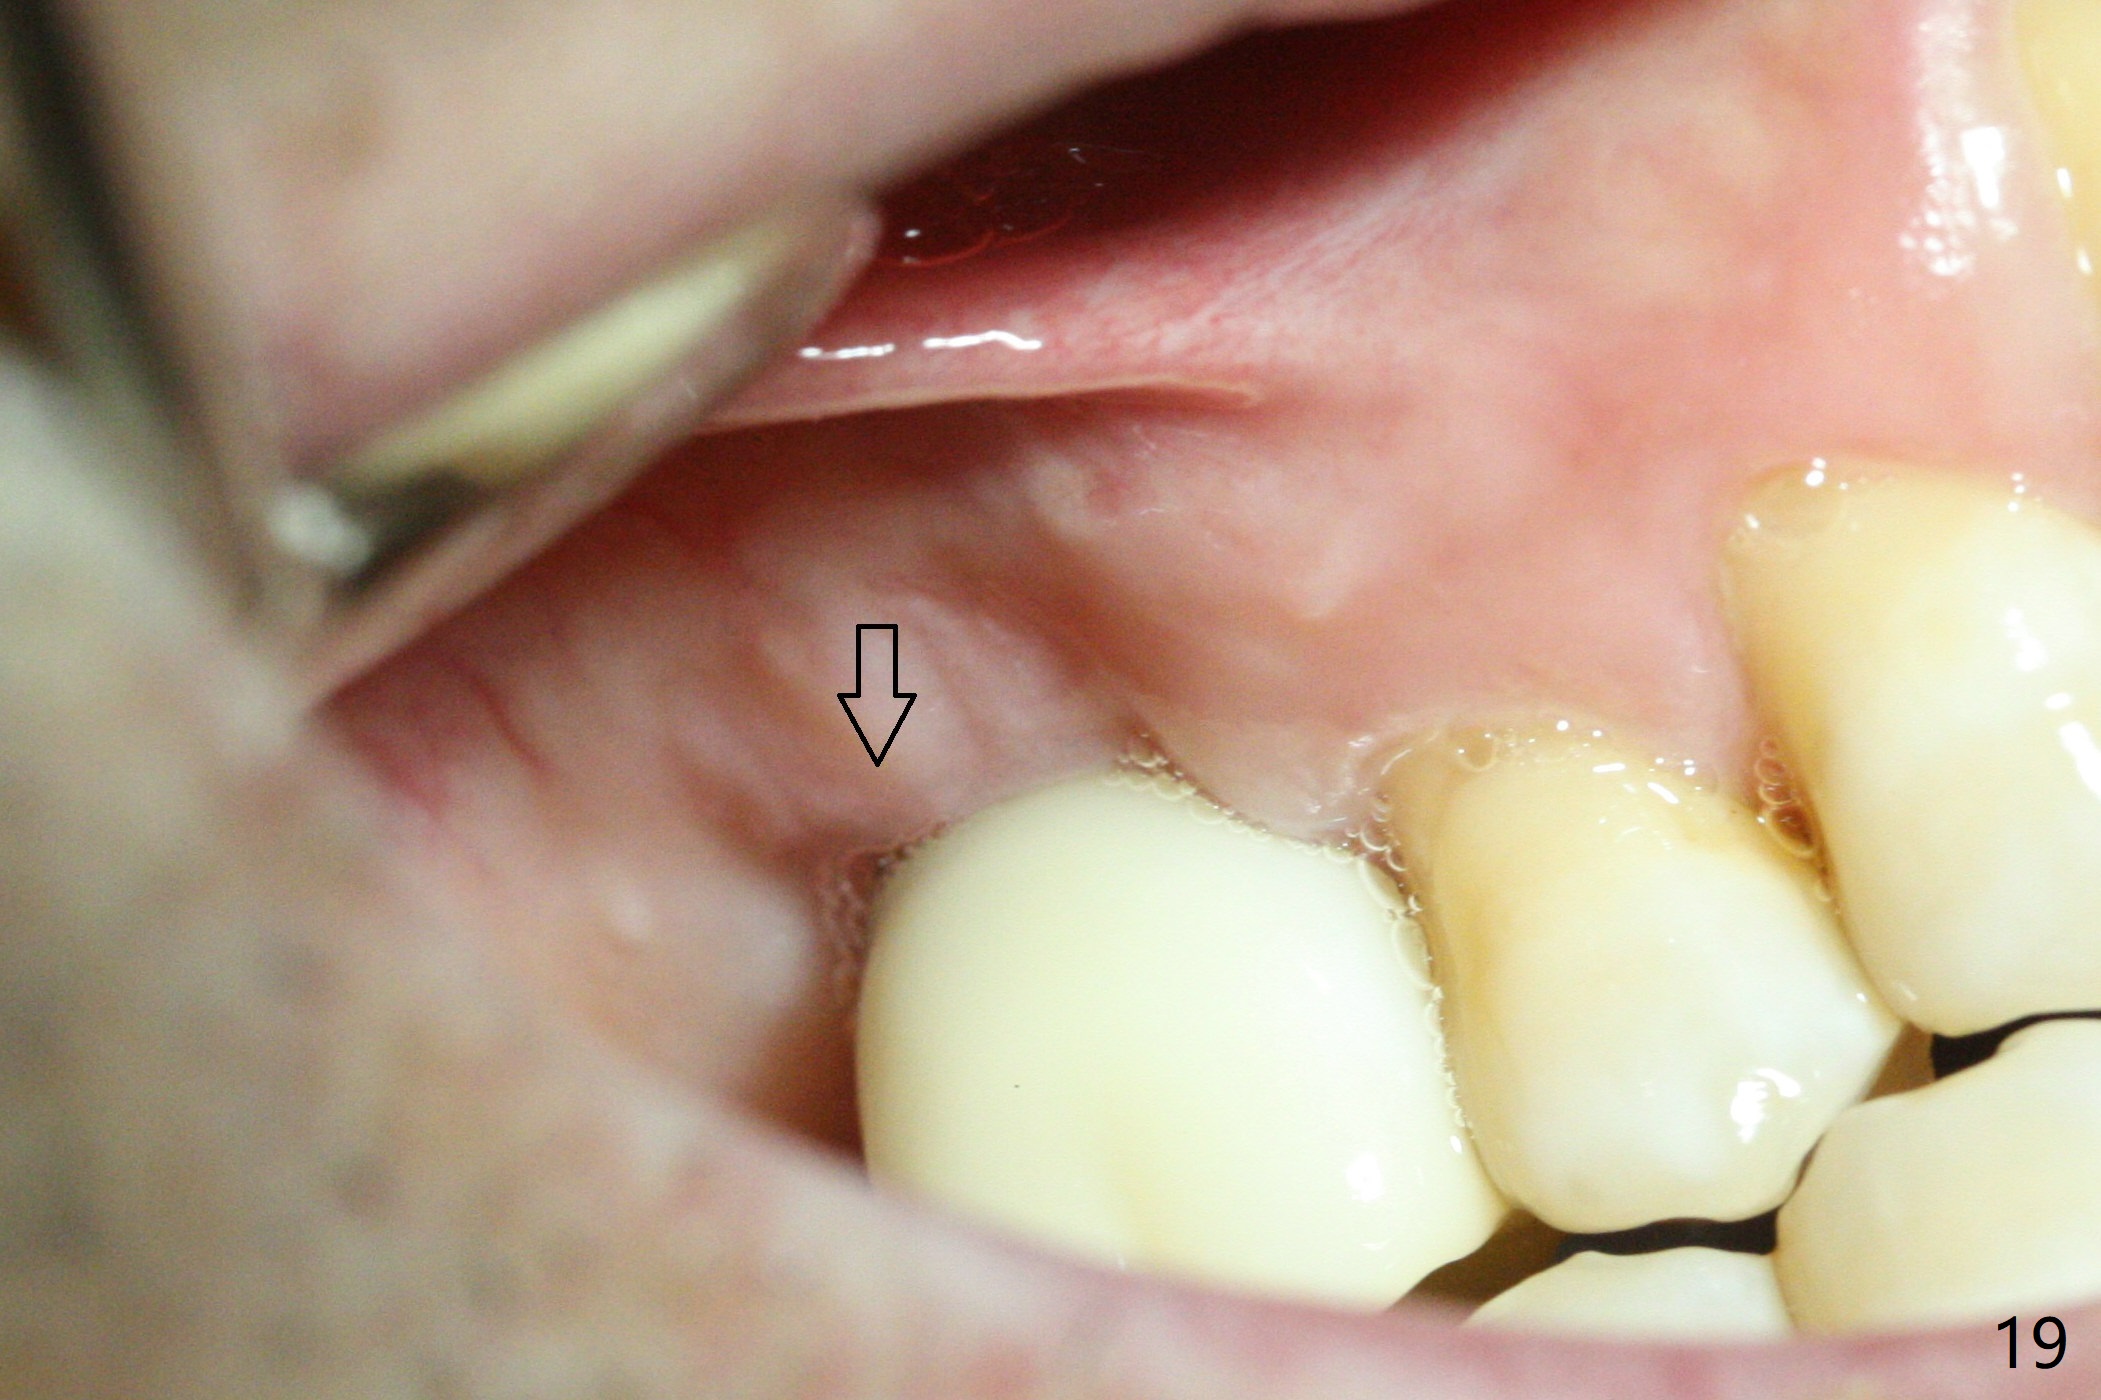

Two weeks later, the buccal gingiva appears to have grown downward (Fig.13). Fig.14 is taken when the provisional is removed. To facilitate this process, change abutment from 4.8x7(3) to (4.5) mm and a new provisional is fabricated (Fig.15): note the metal exposure distobuccally. When the patient returns in another two week, the gap should be able to disappear. There is no loss of bone graft 3 months postop (Fig.16). Two weeks later (3.5 months postop), the margin of the abutment is supragingival buccally and subgingival palatally (Fig.17,18). The gingiva seems to have migrated downward (Fig.19 arrow), while the bone density around the coronal implant appears to increase 5.5 months post cementation (Fig.20). There is buccal swelling with purulent discharge 1.5 years post cementation (Fig.21). Perimplantitis develops. Tuberosis bone graft will be performed when the limited ortho is finished.